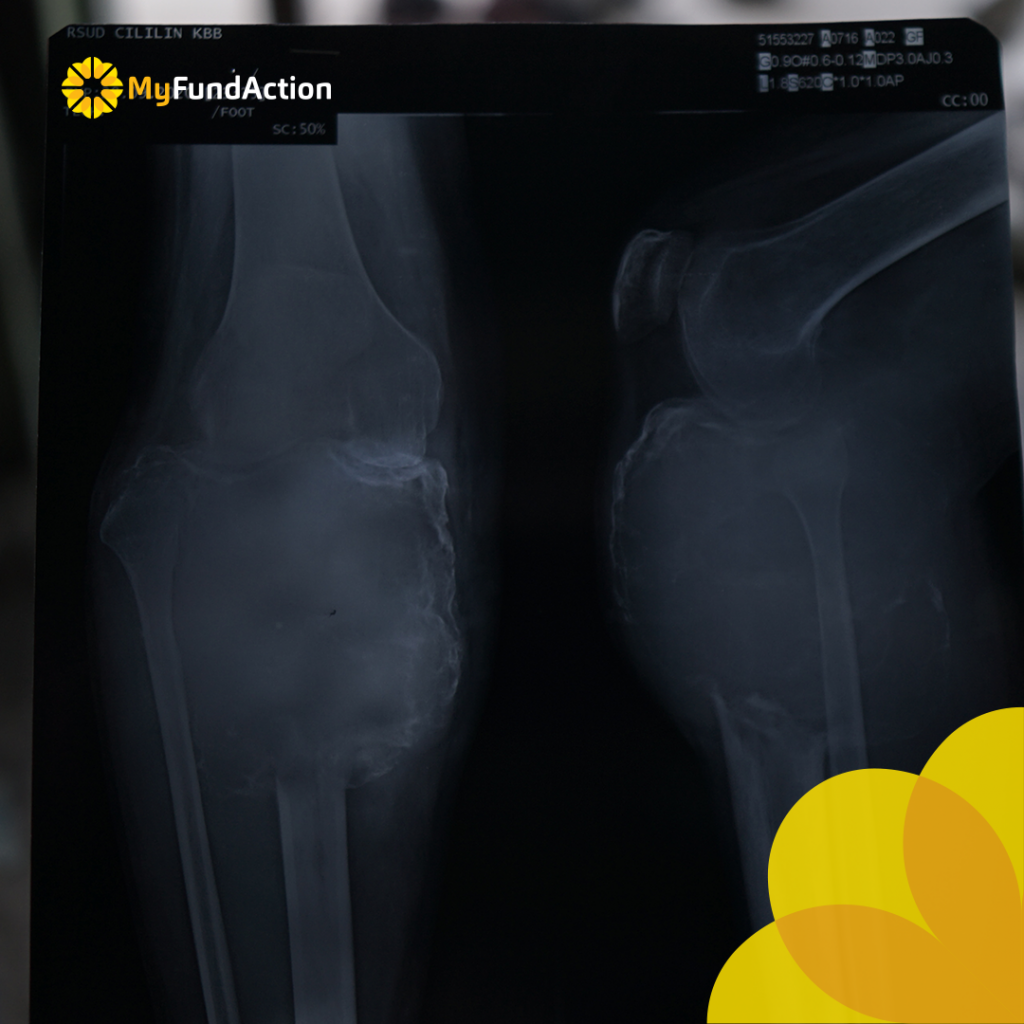

Sampainya di Rumah Sakit, Kang Gumilar mendapatkan diagnosa Giant Cell Tumor of Bone a/r Proximal Tibia Dextra, dan harus melakukan operasi secepatnya. Operasi direncanakan pada 22 Desember 2020 di Rumah Sakit Hasan Sadikin Bandung.